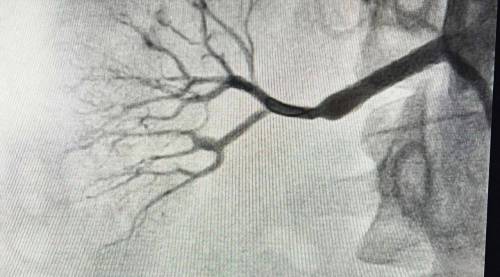

«Это уникальный случай, с которым мы столкнулись впервые. Фиброз практически полностью перекрыл правую почечную артерию. Мы провели углубленную КТ, убедились, что почка сохраняет функцию, и приняли решение срочно оперировать. Без вмешательства орган был обречён», — рассказал рентгенэндоваскулярный хирург ПККБ №1 Вячеслав Воробьёв.

Для операции специалисты заказали индивидуальный стент, способный выдержать высокое давление. Вмешательство выполнил заведующий отделением рентгенохирургических методов диагностики и лечения РСЦ Никита Грачёв. Процедура длилась около получаса и завершилась успешно.